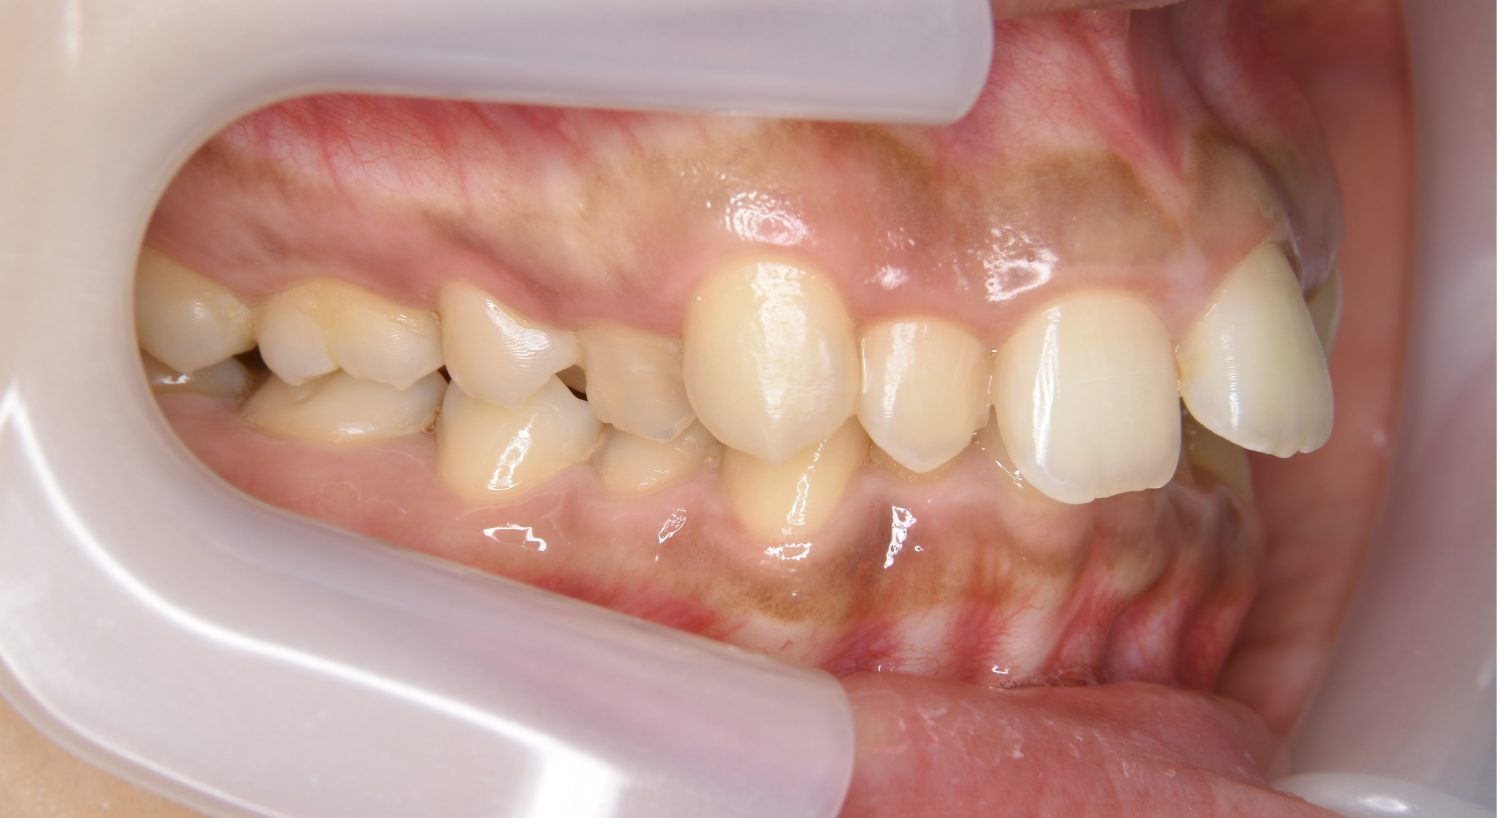

上顎前突の症例紹介①

Before

主訴

上の歯が出ている。歯並び全体が気になる。

治療内容

上顎両側第一小臼歯を抜歯し、上下ラビアルブラケット(唇側装置)に矯正用アンカースクリューを併用し治療を行いました。

上顎前歯の前突により口元の突出が認められました。上の左右の第一小臼歯を抜歯し上顎前歯を後退させることで口元の突出感は改善し、咬合も良好な状態となりました。